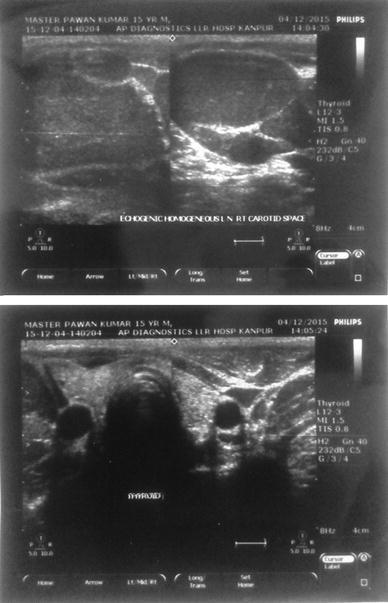

A fifteen year old boy was presented to our hospital with chief complaints of painless progressive swelling in the right side of neck in last 6 months. Patient was having no history of fever, pain in throat, difficulty in deglutition, difficulty in respiration, chronic cough, loss of appetite or loss of weight. On examination there was non-tender, non-fluctuant soft to firm swelling involving anterior and posterior triangle of neck about 10 × 6.5 cm in dimension on right side. It was mobile and not adherent to underlying skin (Figs. 1, 2). There was also swelling involving bilateral supraclavicular region. There was no any swelling in axillary or inguinal region. On nasal endoscopy no abnormality was detected. Routine haematological examination showed Haemoglobin 12.2 g%, Total leukocyte count 6.3 × 109/litre, Erythrocyte sedimentation rate 15 mm 1st hour while differential leukocyte count was with in normal limits. Mantoux test was negative. High resolution Ultrasonography suggested multiple discrete, homogenous lymph node in right carotid space. There was no cystic necrotization, calcification or loss of fibrofatty plane are seen (Fig. 3). Contrast enhanced computed tomogram neck with thorax suggested a large lobulated soft tissue lesion about 10 × 6.5 × 5.5 cm in dimension (Fig. 4). No intratumoral necrosis was seen. Patchy heterogeneous enhancement was seen in post contrast images. Mass was mildly compressing trachea and right thyroid gland to the left (Figs. 5, 6). Bilateral supraclavicular lymph node was seen along with non-necrotic lymph node in superior mediastinum. Fine needle aspiration cytology from cervical lymph node was highly suggestive of Rosai–Dorfman disease, however biopsy was advised for confirmation. Biopsy was done under local anaesthesia from the posterior triangle of neck just behind the mid part of sternocleidomastoid muscle. Histopathology showed diffuse effacement of lymph node architecture and dilated sinuses distended with benign histiocytes (Figs. 7, 8); the diagnosis was given as sinus histiocytosis with massive lymphadenopathy (Rosai–Dorfman disease). This patient was put on oral prednisolone 10 mg three times a day in tapering doses for 21 days initially and then on low dose of steroids for next 4 months. The patient showed marked clinical improvement.

Fig. 3.

High resolution ultrasonography of neck